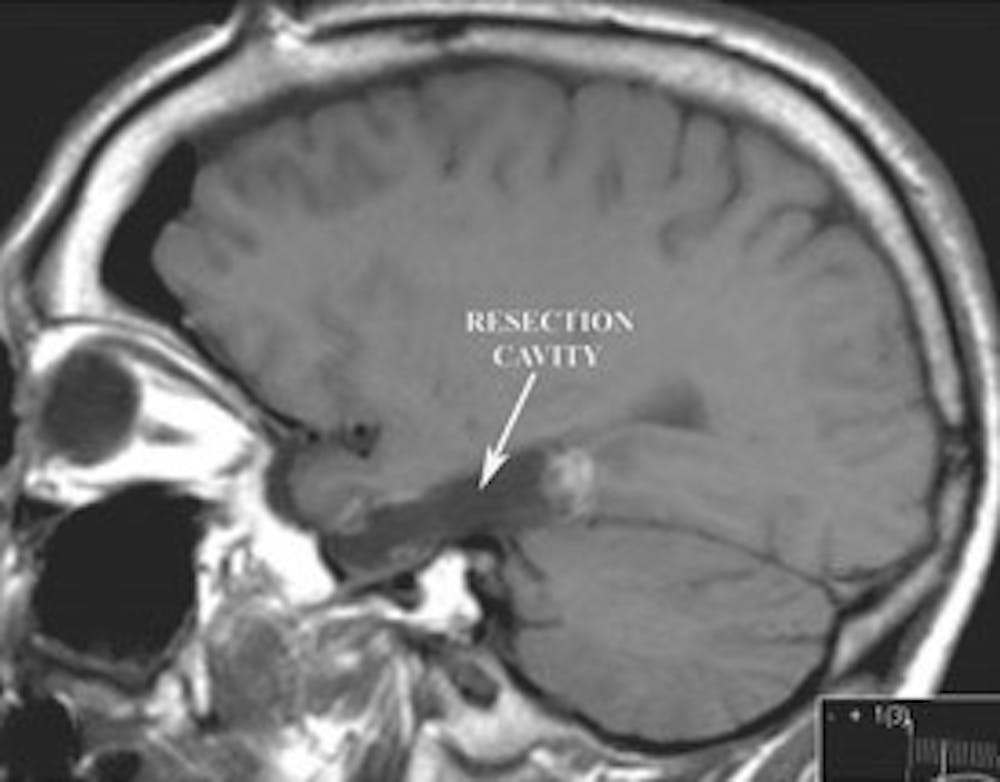

बी) पोस्ट-ऑपरेटिव सैजिटल टी1 भारित एमआरआई हिप्पोकैम्पस के उच्छेदन को प्रदर्शित करता है